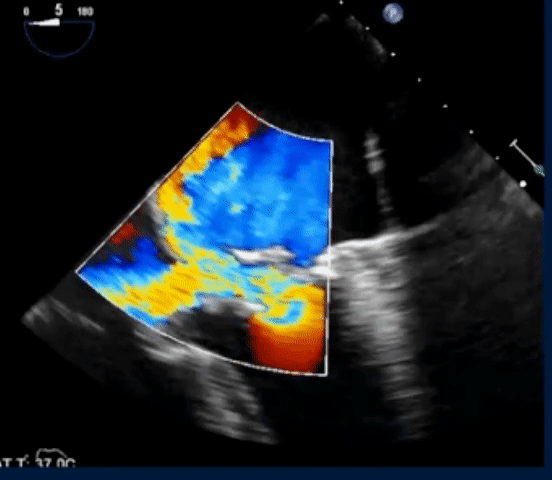

- The following TEE with color Doppler shows a jet of MR going into the LA and RA

- TEE